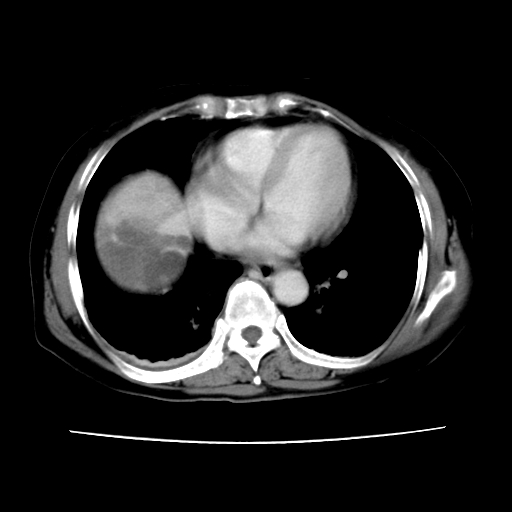

2008-6-10ct平扫

ct增强

6月片:肝血管瘤并破裂出血?肝左外叶囊肿

考虑肝腺瘤出血可能,肝血管瘤增强表现不是很典型,放在第二。

考虑为肝血管瘤破裂出血并肝包膜下血肿;右侧少量胸腔积液。

6月份ct片显示肝内巨大混杂密度团块,伴包膜下积液(内含液液平面),增强多无明显强化。只能考虑肝占位病变,并肝内、血膜下血肿。肝ca并出血多见,而肝血管瘤并破裂出血少见。